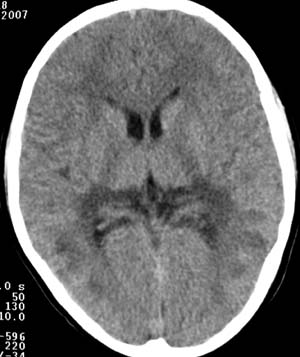

两侧颞枕叶脑白质区多发斑片状低密度灶,考虑脑白质病变;肾上腺脑白质营养不良可能大。

1,发病年龄相符,5-10y。2,临床有视、智力改变。3,病灶发病位置相符;大脑后部白质,侧室三角区周围,对称。

两侧脑室后角旁、丘脑、放射冠、颞顶叶呈对称性片状低密度影,脑室系统、环池、四叠体池、脑桥小脑角池偏大。

病灶从后向前发展,结合临床表现,首先考虑:肾上腺脑白质营养不良。

两侧脑室后角周围髓质,丘脑,放射冠,及颞顶区可见对称的低密度区,侧脑室后角未见明显扩大

诊断:肾上腺营养不良性脑白质病